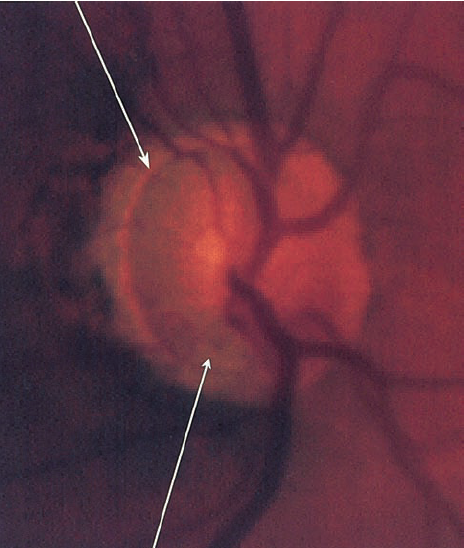

2.2. Gai thị

Tổn hại gai thị không có sự khác biệt với các loại glôcôm khác như tỉ lệ C/D lớn, tổn hại lớp viền thần kinh đĩa thị giác, thay đổi mạch máu của đĩa thị giác…Tuy nhiên, trong glôcôm nhãn áp bình thường tổn hại gai thị cũng có 1 số đặc điểm riêng:

- Lớp viền thần kinh quanh gai thị mỏng hơn so với glôcôm nhãn áp cao.

- Lõm gai không quá sâu và lớp lá sàng ít bị đấy ra phía sau hơn.

- Hay gặp tổn hại viền thần kinh gai thị khu trú ở 1 vị trí kèm theo lõm gai thị sâu và thay đổi lớp lá sàng tạo thành hố gai thị mắc phải, 75% gặp ở glôcôm nhãn áp bình thường so với 15% ở glôcôm nhãn áp cao.

BSVL1

Teo lớp sợi thần kinh quanh gai thị

Mất lớp viền thần kinh

Xuất huyết cạnh gai thị

- Một trong những dấu hiệu thường gặp nhất trong glôcôm nhãn áp bình thường  là teo võng mạc cạnh gai thị ( vùng α và vùng β), tuy nhiên dấu hiệu này không đặc hiệu cho glôcôm nhãn áp không cao .

- Xuất huyết gai thị: rất hay gặp trong glôcôm nhãn áp bình thường.

- Tổn hại lớp sợi thần kinh quanh gai thị: hay gặp tổn hại lớp sợi thần kinh khu trú ở 1 vị trí nào đó hơn là tổn hại toàn bộ chu vi gai thị.

Tuy nhiên,  những dấu hiệu trên không đặc hiệu cho glôcôm nhãn áp bình thường , không cho phép chẩn đoán xác định mà chỉ có giá trị gợi ý glôcôm nhãn áp bình thường  mà thôi.